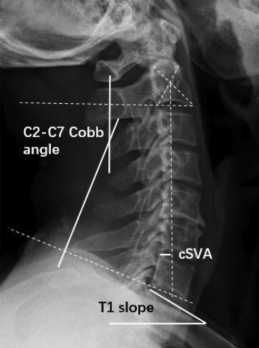

以T1 SLOPE 代表整体平衡,以CSVA代表颈椎平衡,整体平衡良好,颈椎局部平衡就能维持:

颈椎矢状位参数

整体矢状位参数